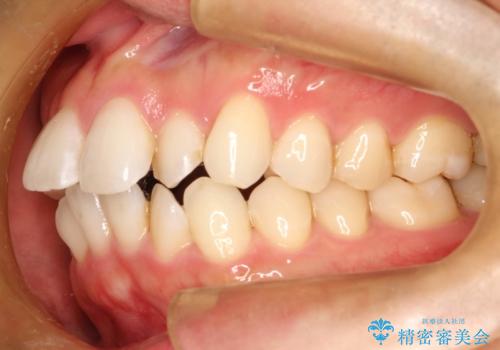

フルリンガル矯正 非抜歯でガタつきを整える

- フルリンガルワイヤーによる非抜歯治療を計画しました。